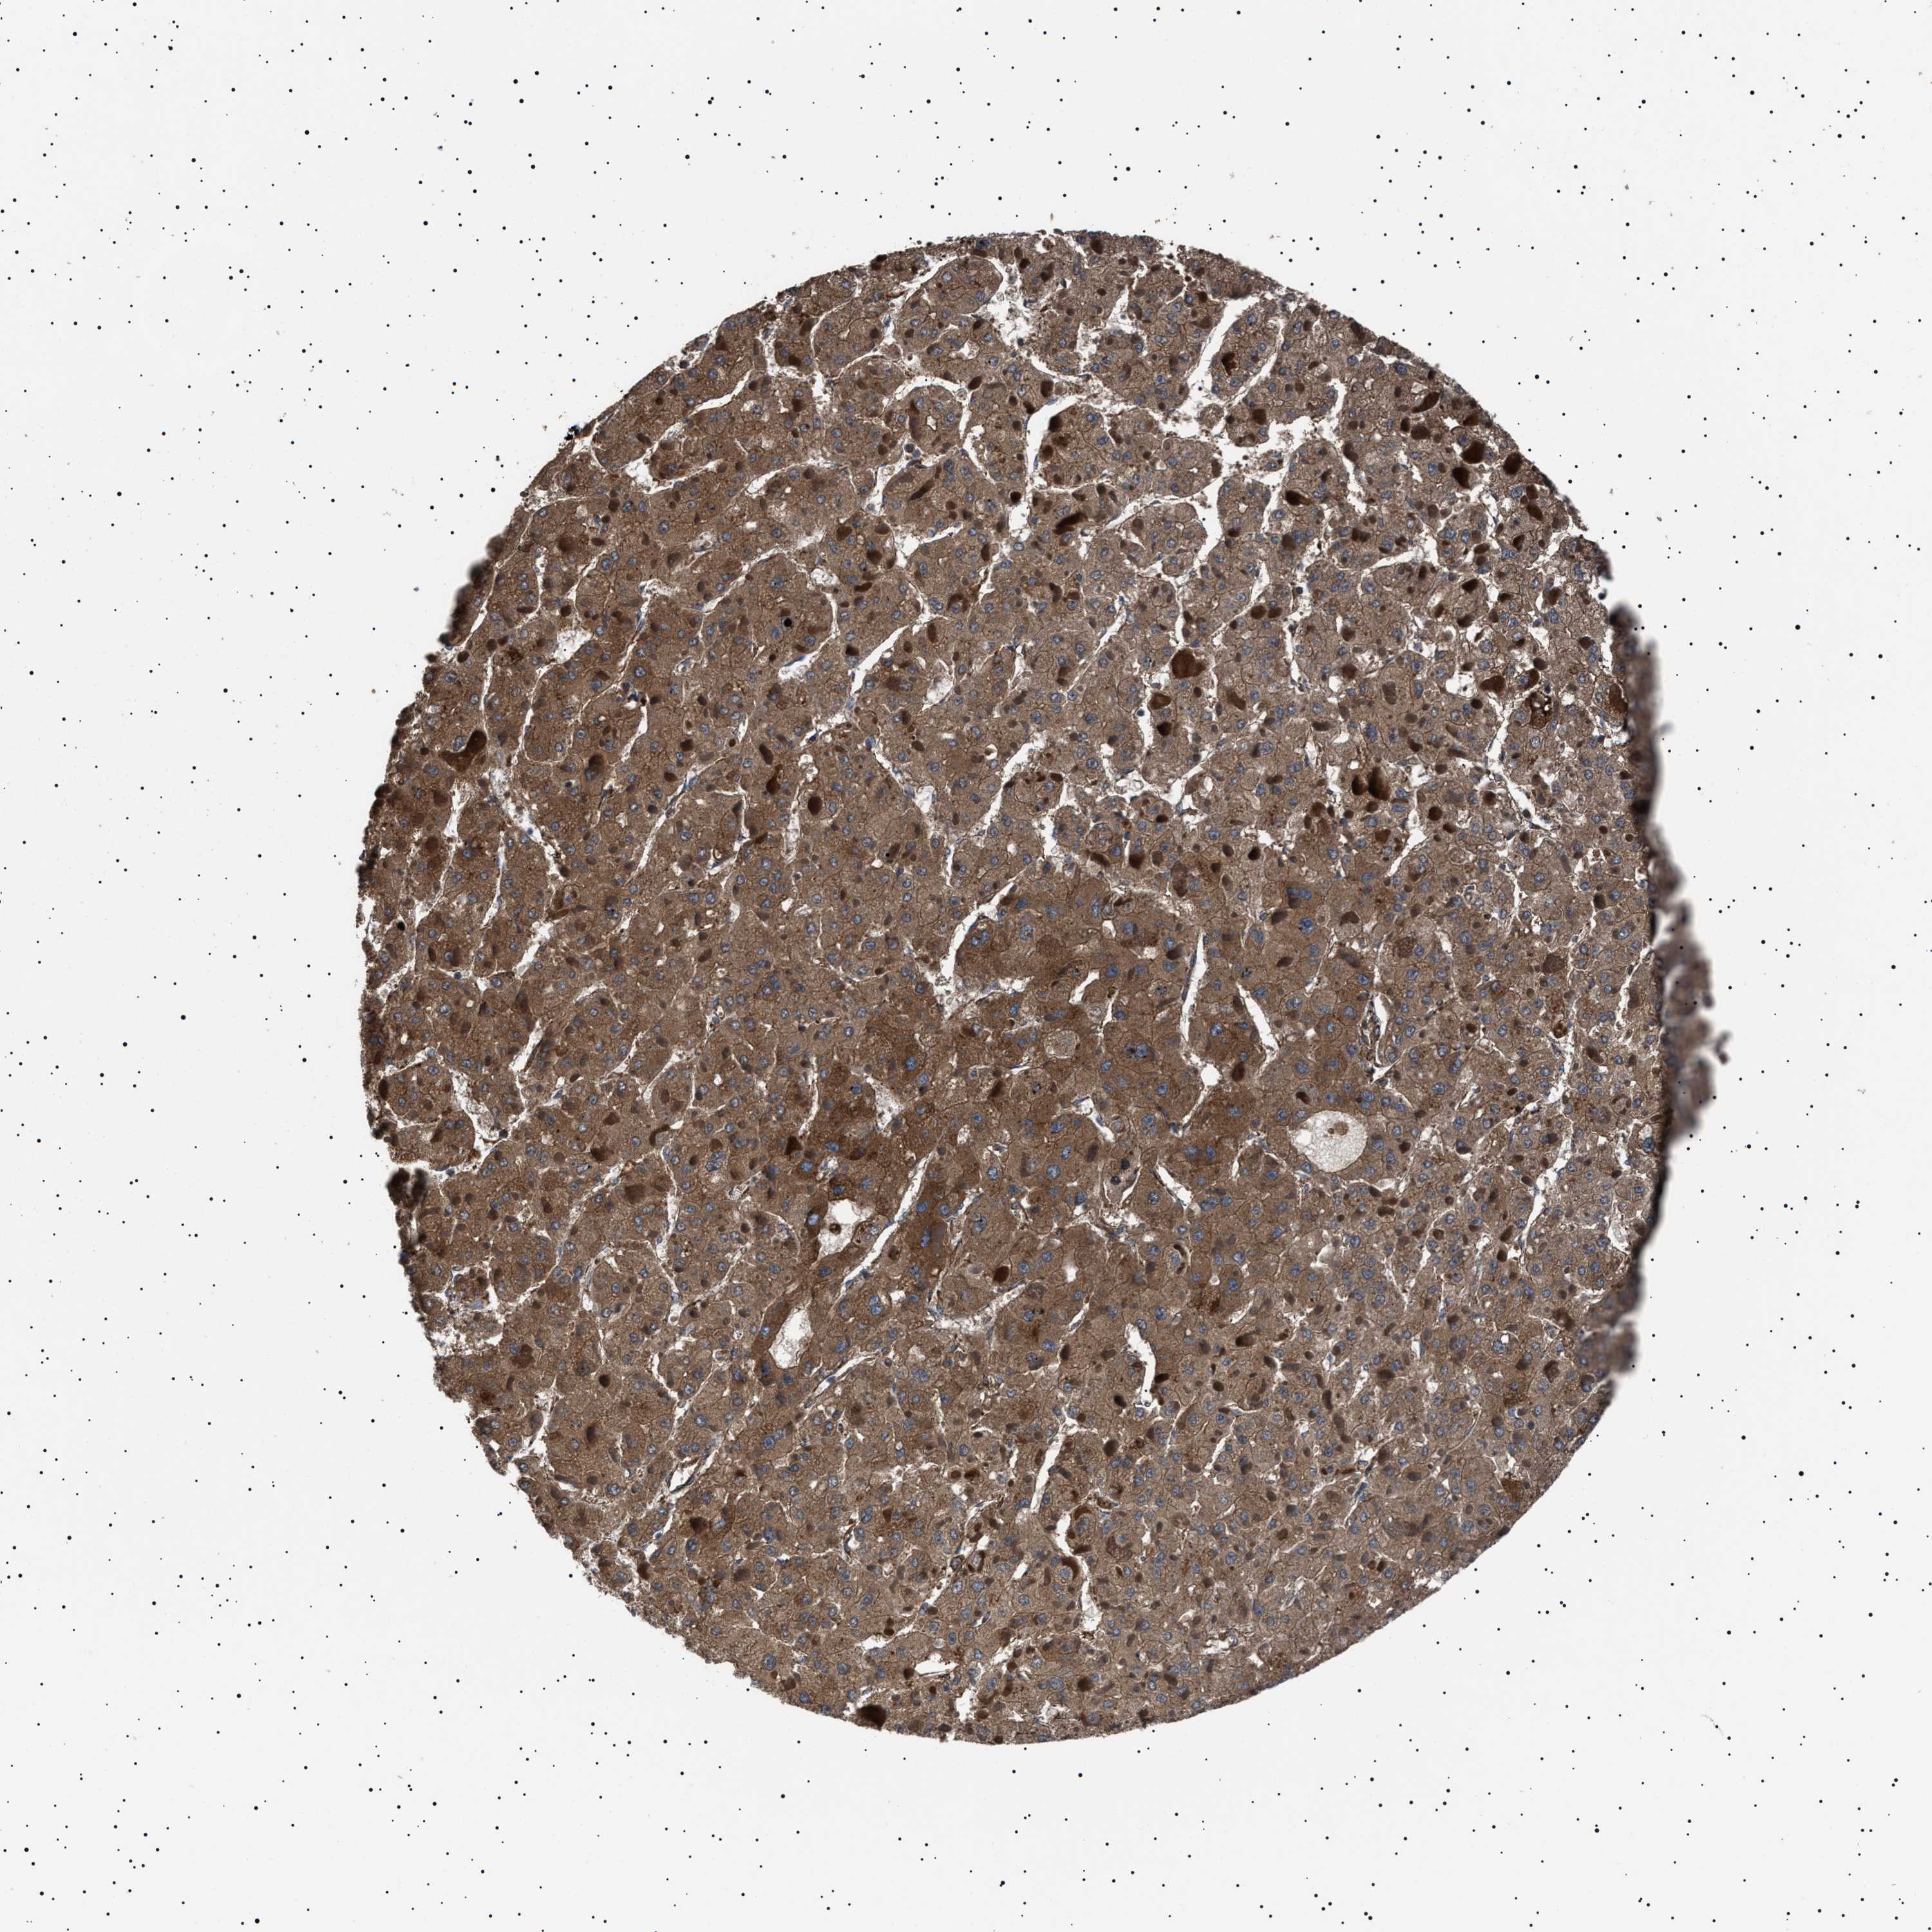

LIVER CANCER - Protein expressioni

A mouse-over function shows sample information and annotation data. Click on an image to view it in a full screen mode. Samples can be filtered based on level of antibody staining by selecting one or several of the following categories: high, medium, low and not detected. The assay and annotation is described here.

Note that samples used for immunohistochemistry by the Human Protein Atlas do not correspond to samples in the TCGA dataset.

Antibody stainingi

Antibody staining in the annotated cell types in the current human tissue is reported as not detected, low, medium, or high, based on conventional immunohistochemistry profiling in selected tissues. This score is based on the combination of the staining intensity and fraction of stained cells.

Each image is clickable and will lead to virtual microscopy that enables deeper exploration of all samples and also displays staining intensity scores, fraction scores and subcellular localization as well as patient and tissue information for each sample.

Antibody HPA001915

Antibody HPA021542

Staining

High

Medium

Low

Not detected

Intensity

Strong

Moderate

Weak

Negative

Quantity

>75%

75%-25%

<25%

None

Location

Nuclear

Cytoplasmic/membranous

Cytoplasmic/membranous,nuclear

Cholangiocarcinoma

Carcinoma, Hepatocellular, NOS